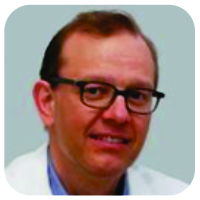

The ACL was still intact yet showed a discrete laxity. No other fractures or injuries were visualized. Furthermore, the joint was rinsed and the loose bone fragments were removed to improve thee xtension and deep flexion. Peroperatively, the ROM was tested and was complete. Postoperatively, the knee was immobilized in extension with a hard cast. Weight-bearing was not allowed. Physiotherapy was established to strengthen and stabilize the knee. In the first follow-upconsultation 1 week after surgery, a new hard cast was applied for one more week. The patient was instructed to continue the isometric exercises for adequate revalidation. After 2 weeks of cast immobilization, an extension brace was applied for another 2–3 weeks. 6 weeks after the initial trauma, clinical examination showed a positive clinical course. A follow-up CT scan was performed (Fig. 4) that could show a starting consolidation. A CT scan examination was discussed with the family of our patient since his wish was to start sporting (football) early. Furthermore, CT scan is superior to X-ray with the disadvantage of a higher radiation dose. The extension brace was removed and a soft walking brace was applied. The patient was allowed to walk by full weight-bearing, taking pain and stability into account. A T1-weighted magnetic resonance imaging (MRI) scan was performed at 8weeks of follow-up (Fig. 5).This examination was initially performed because of a new trauma and was ordered by the general practitioner. However, it is useful to present the result of the MRI in this case report. The MRI showed an almost complete consolidation alongside very limited edema of the bone (Fig. 5a and b). The ACL and posterior cruciate ligament (PCL)weretotally intact (Fig. 5c and d). Clinically, the knee showed normal stability. The walking brace was permanently removed, and the patient was allowed to perform routine daily activities including all sportive activities. No more follow-up consultations were planned.